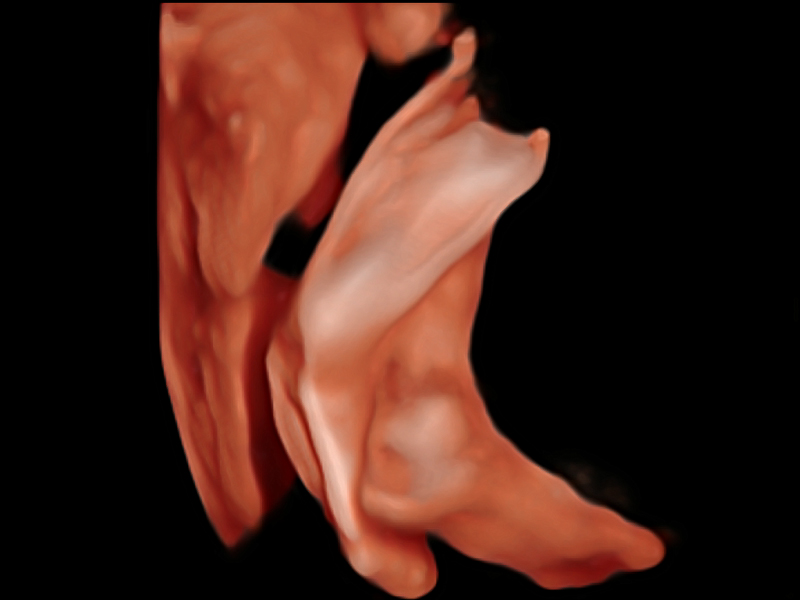

自动识别收缩和舒张末期心肌内膜,自动计算射血分数EF值。